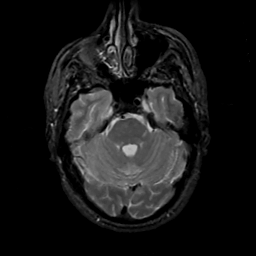

MR Study #14, June 2, 1991 -- Slice #14